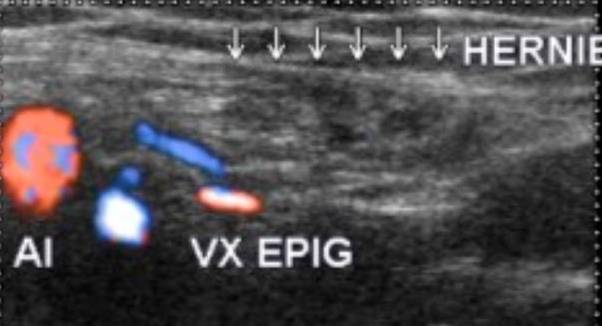

Cautarea herniiloringhinale ecografic se face la nivelul ostiumului arterei epigastrice inferioare, la un pacient culcat si relaxat Daca cautarea este negativa se cere pacientului efectuarea manevrei Vasalva.

Herniile inghinale indirecte sunt mai frecvente (65% Ele corespund unui sac peritoneal care se exterioreaza prin foseta inghinala externa in afara vaselor epigastrice. Coletul herniar este in pozitie antero-laterala in raport cu ostiumul arterei epigastrice inferioare. Aceste hernii inghinale indirecte se intind mai mult sau mai putin in lungul cordonului pana la nivelul scrotului realizand o hernie inghino-scrotala

Hernie indirecta